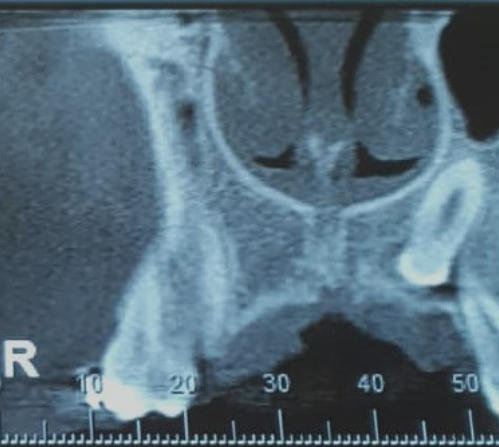

Veja alguns casos de sucesso